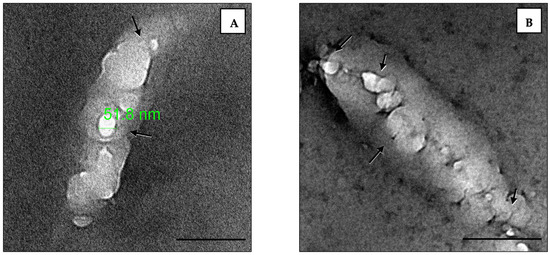

3.4. TEM Imaging of Empty Liposome–Bacterial Membrane Fusion